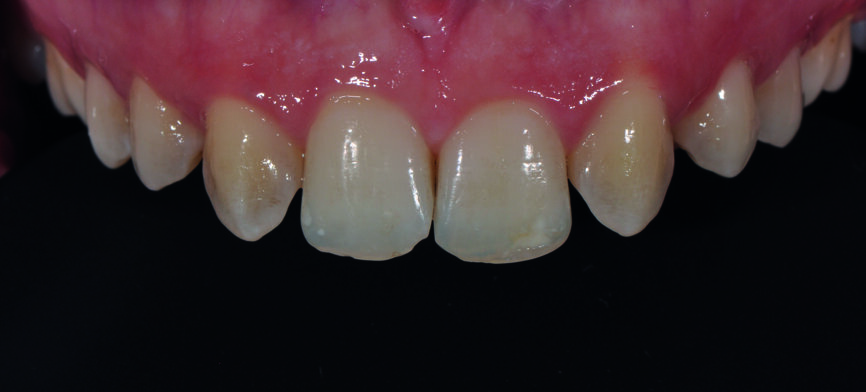

Fig. 4 : a) Gros plan du sourire avant le traitement.

Fig 4b) : vue intraorale latérale.

Fig 4c) : vue intraorale de face.